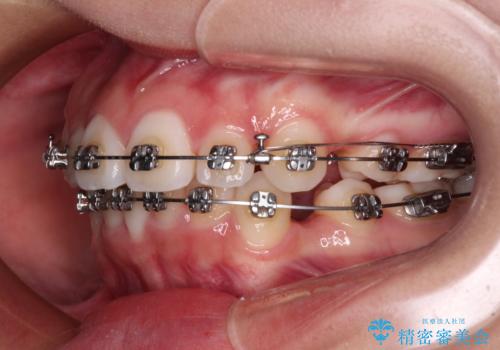

- 歯のデコボコや八重歯、クロスバイトを気にして来院された患者様です。

上下左右第一小臼歯4本を抜歯し、ワイヤー装置にて歯列を整え、さらには少しでも口元を引っ込めるよう矯正治療を行うこととしました。

上下の骨格での左右差が小さかったことと、抜歯矯正であったことで、上下正中の位置をきれいに合わせることができました。